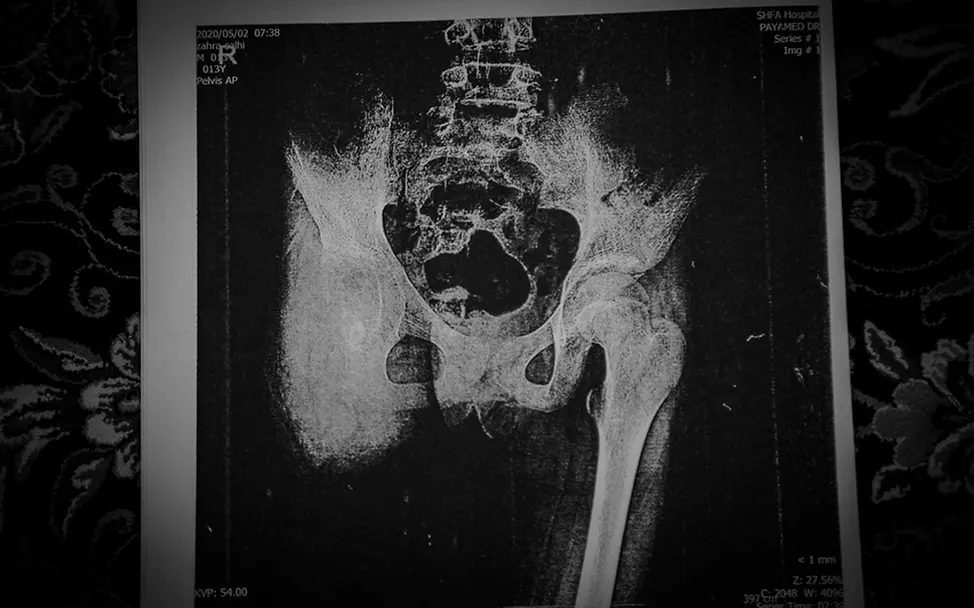

Davon träumte Zahra: Sie wollte so leicht sein wie ein Schmetterling. Und fliegen. Eines Tages. In dieser Welt aber wird ihr Traum nicht mehr in Erfüllung gehen. Nur 13 Jahre alt ist Zahra geworden, die letzten drei davon hat sie mit aller Tapferkeit gegen eine Krebserkrankung der Knochen gekämpft. Einen Kampf in furchtbaren Etappen. Beginnend mit einer Chemotherapie, die so vergeblich war, dass dem Mädchen zunächst das rechte Bein amputiert werden musste, dann eine Lendenwirbel-Operation nötig wurde, die zu einer Querschnittslähmung führte.

Der iranische Fotograf Shayan Hajinajaf hat den Leidensweg des Mädchens ebenso intensiv wie sensibel begleitet: Momente, in denen Zahra lächelte, und solche, in denen sie kaum noch Luft bekam; die Trostaugenblicke in der Familie und das Alleinsein im Krankenhausbett, Gehversuche am Anfang und die Agonie am Ende. Nach Angaben der iranischen „Children’s Blood and Cancer Association“ erhalten jährlich etwa 2500 Kinder unter 15 Jahren die Diagnose Krebs.